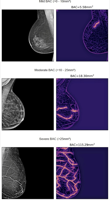

Researchers say AI could help save the disproportionate number of women who have undiagnosed and untreated heart disease.